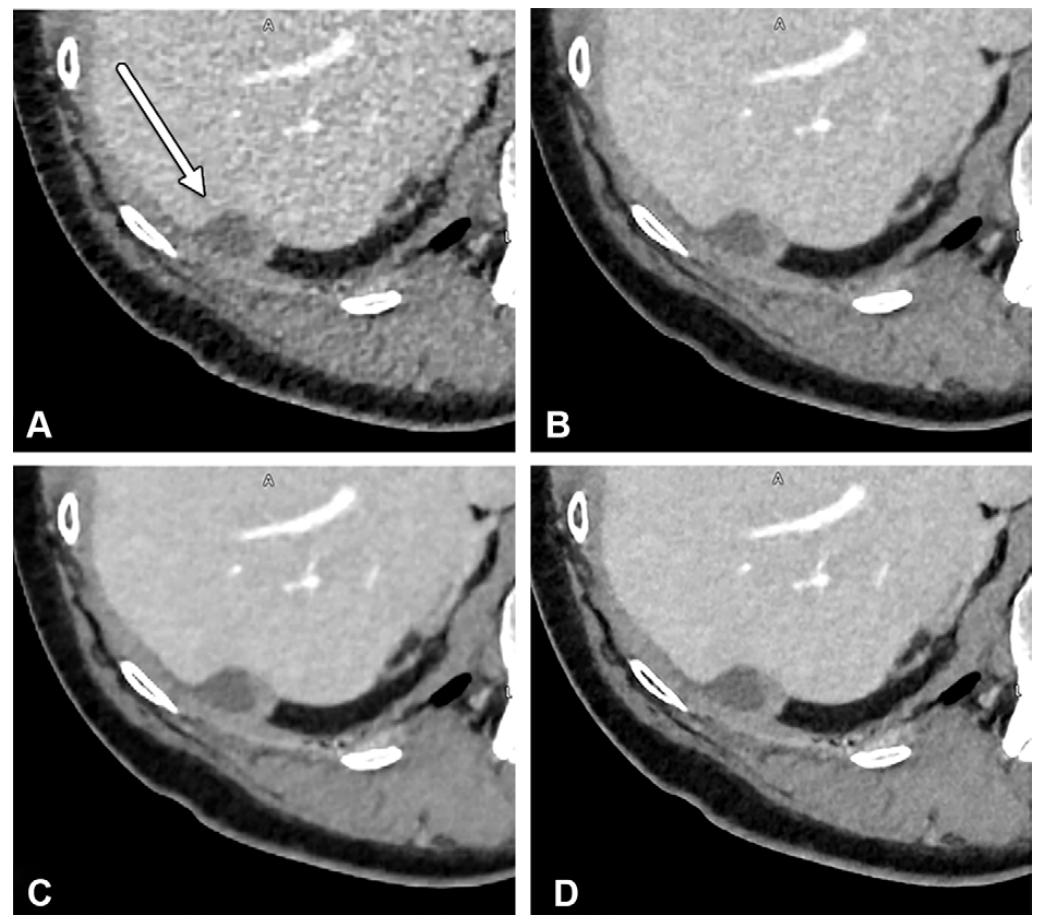

轴位增强 CT 图像显示一名研究参与者肝脏内的结直肠癌转移瘤(B 图箭头所示)。采用中等强度 TrueFidelity DLR 重建的图像(A 图),即使辐射剂量降低 66%,病变显影度仍略有提升,且与同一屏气状态下获取的标准剂量 FBP 图像(B 图)相比,该病变在标准剂量 FBP 图像中被阅片者遗漏,而在 DLR 图像中被成功识别。